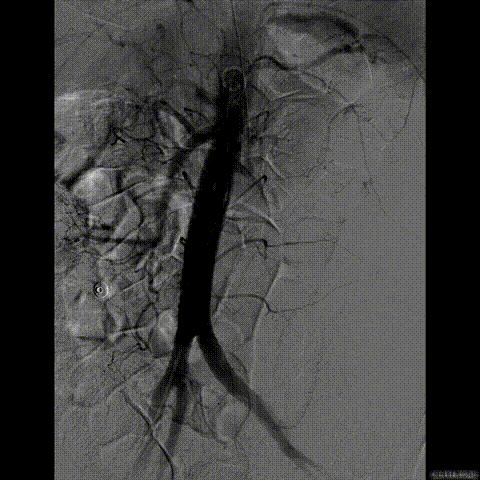

行急诊手术 腹主动脉及左侧股动脉造影

左侧股动脉见造影剂外渗

球囊压迫后植入覆膜支架

复查造影